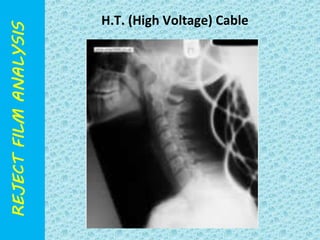

H.T. (High Voltage) Cable